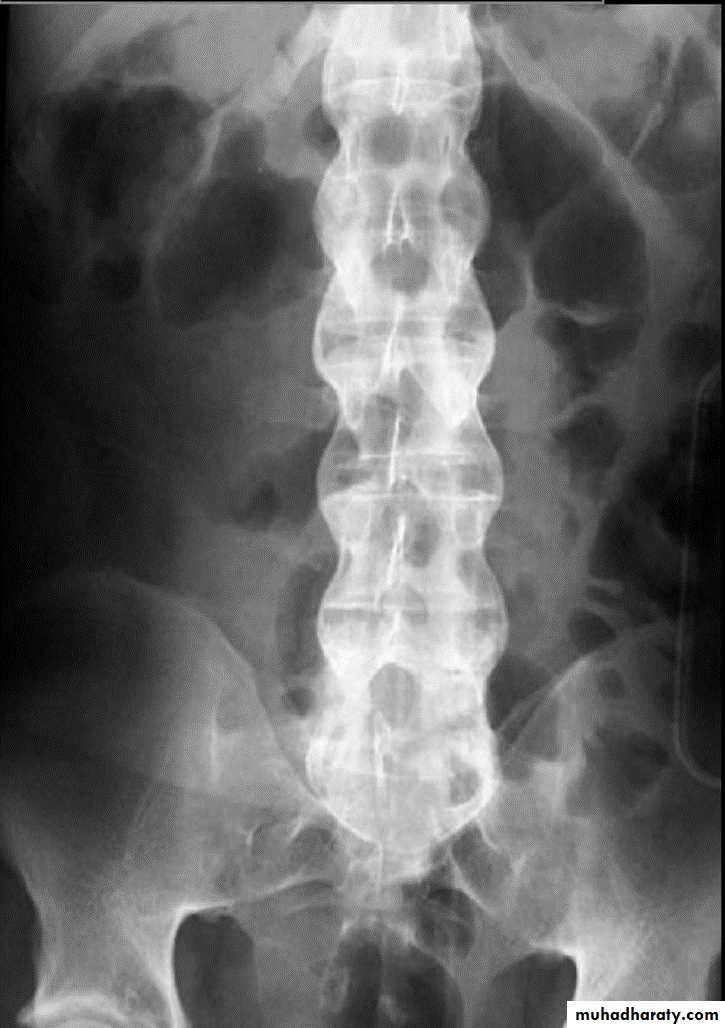

* Syndesmophytes

* Bamboo spine: late fusion and Bamboo spine

ligamentous ossification